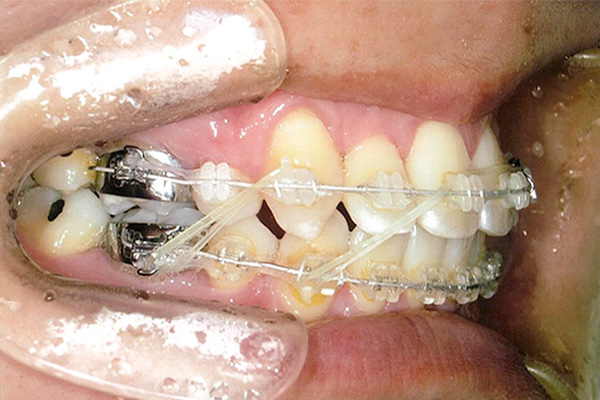

症状八重歯+二重歯列による噛み合わせ不具合

抜歯あり

6ヶ月後